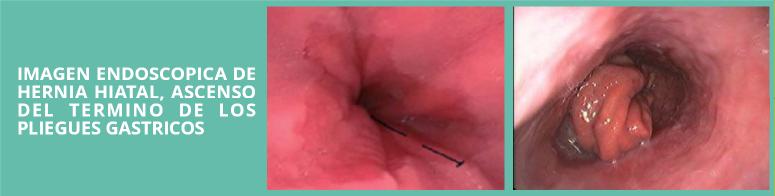

Hernia Hiatal

La hernia de hiato se produce cuando la porción superior del estomago asciende hacia el tórax a través de una pequeña abertura que existe en el diafragma (hiato diafragmático)" El diafragma es el músculo que separa el tórax del abdomen. El hiato diafragmático es parte de la barrera anatómica que separa el esófago del estómago

El diagnóstico de una hernia hiatal comienza con el examen físico por razón de la sintomatología. La radiografías de abdomen con contraste y estudios endoscópicos (la video-endoscopia digestiva con observación directa del esófago y estómago) demuestran la hernia hiatal y ayudan a descartar otras causas de molestias digestivas altas.